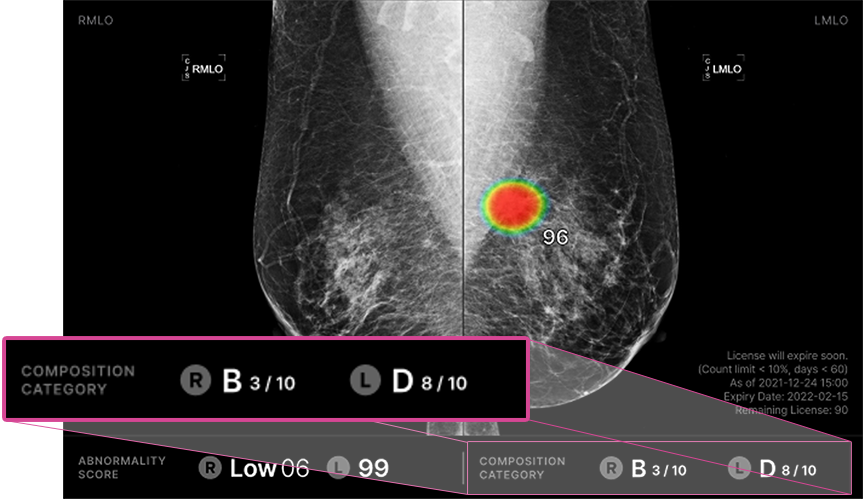

Lunit INSIGHT MMG accurately detects lesions suspicious of breast cancer in a mammogram.

Lunit INSIGHT MMG automatically analyzes and generates quantitative density assessment* during breast screening.

Lunit INSIGHT MMG successfully analyzed the mammogram of an overlooked case in 2020, where cancer was missed and the patient was diagnosed 2 years later in 2022.